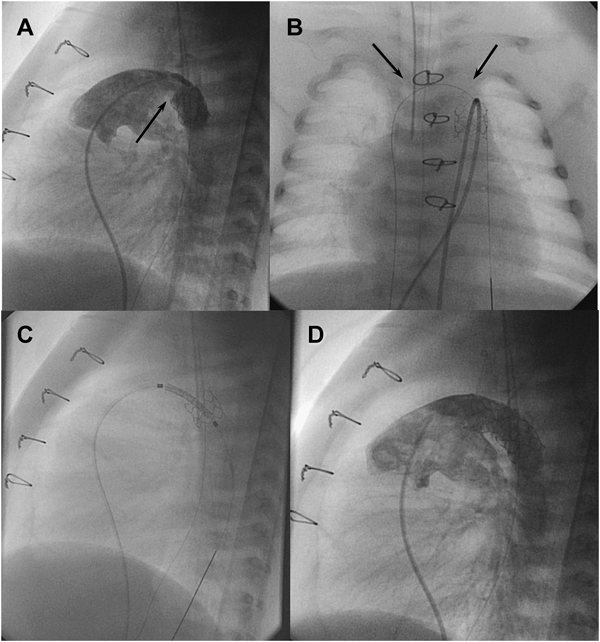

通常のBASが困難,危険,無効な状況としては,肥厚した心房中隔壁,intact atrial septum(IAS),小さいLA,低体重児,両側FVの閉塞・IVC離断などがある.肥厚した心房中隔壁に対して以前はblade atrial septostomyが施行されたが,心房壁や右室流出路(RVOT)の裂傷から死亡する合併症があり,近年はあまり施行されなくなっている2,3).これに対してballoon atrial septal dilationは効果がやや劣るが安全に施行できる.有効な欠損孔を得るためには新生児でも10~12 mm径のバルーンが必要である4,5).inflation/deflationが素早くできるArmada(12 mm×20 mm; Abot)などが適している.当院での経験になるが,Balloon atrial septal dilationにBASを組み合わせることで十分な効果が得られている.IASに対して日本では昨年までBrockenbrough needleを使用せざるを得なかった.新生児・乳児の体格でも心房中隔穿孔は不可能ではないが,特にHLHSでは心房中隔壁が厚く,それを穿孔するだけのLA容積(奥行き)がない場合が多く(Fig. 2),心房壁の穿孔・心タンポナーデの合併率が高くなる6,7).欧米では10数年前からradiofrequency wireを用いた心房中隔穿孔が施行されている(Fig. 3)8).心房中隔に接触させて通電するだけで中隔を穿孔できるので,LAが小さい新生児の肥厚したIASでもより安全に穿孔できる.日本でも2014年8月からNykanen RF wireが使用可能となった(Fig. 4).このwireの直径は0.024″,長さは265 cmで,先端のActive atraumatic tipの直径は0.016″,長さは1.5 mmである.Active tip以外の部分は整形が可能である.Connector cableでGeneratorと接続し,5~10 W,1~10 secの通電で組織の穿通が可能である.現在日本ではPA IVSの肺動脈弁穿孔とIASの心房中隔穿孔に適応があり,その使用には講習が必要である.肥厚した心房中隔のためにBASが無効の場合にはstent septostomyも有効である.留置後抗血小板薬だけでは血栓形成の報告があることから抗凝固療法が必要と思われる9).またstent migrationの報告や強度の内膜増殖を来す期間が不明であり,注意を要する10).

Photograph A shows the left atrial angiogram after transseptal puncture. On transthoracic echocardiogram, immediately before the needle entered the septum, the thick atrial septum (between broken lines) was elongated (broken arrow) and the tip of the needle (arrow) was almost in contact with the left atrial posterior wall (B). Immediately after passing the septum, the tip barely escaped passing through the posterior wall (C; arrow). RA, right atrium; LA, left atrium.